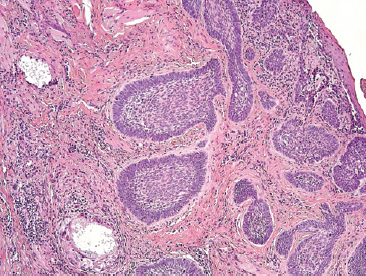

По данным планового морфологического исследования от 21.10.2020: изъязвлённый БКРК, нодулярный тип. Опухоль инфильтрирует сетчатый слой дермы. В краях резекции опухолевого роста не выявлено (рис. 3).

Рис. 3. Фотография гистологического препарата послеоперационного материала пациентки, окрашивание гематоксилином и эозином, ×100

Fig. 3. Photo of the histological specimen of the patient's postoperative material, hematoxylin and eosin staining, ×100